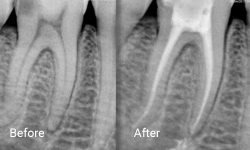

Root Canal Treatment

Root canal treatment, also known as endodontic treatment, is performed to save a tooth that has become inflamed or infected due to deep decay, repeated dental procedures, or trauma. During this procedure, the inflamed or infected pulp is carefully removed, and the inside of the tooth is meticulously cleaned and disinfected.

After cleaning, the tooth is filled and sealed with a rubber-like material called gutta-percha. Finally, the tooth is restored with a crown or filling to ensure long-term protection and functionality. This treatment not only alleviates pain but also preserves the natural tooth structure.